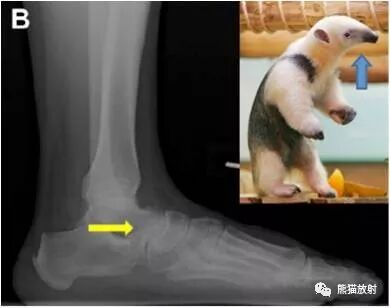

食蚁兽鼻征

1、足侧位X线片上。

2、食蚁兽的鼻子:跟骨的前上部管状伸长,接近舟骨或与其重叠。

3、提示跟舟联合

跟舟联合在侧位X线片上呈现食蚁兽鼻征,拍摄45°内斜位X片观察跟舟联合